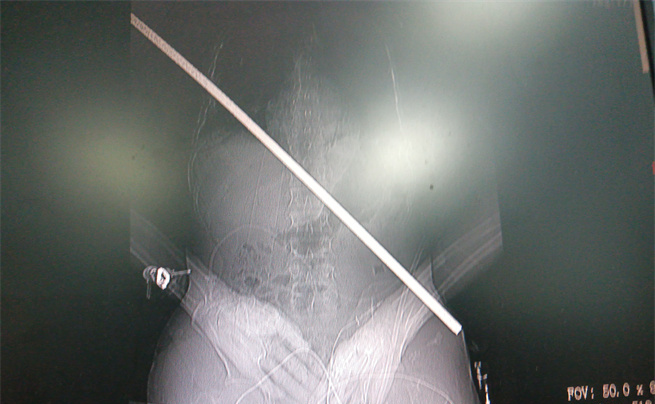

男子身上取出的鋼筋

影像圖。大坪醫院供圖